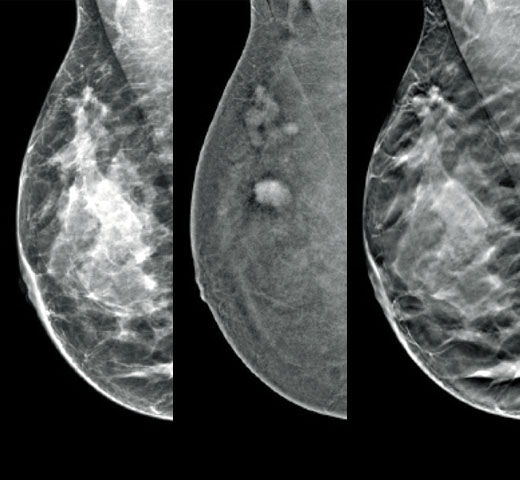

Det är känt att en hög brösttäthet ökar en kvinnas risk för bröstcancer.1 Behovet av noggrann och opartisk analys är därför kritiskt. Med hjälp av maskininlärning analyserar Quantra Technology-programvaran både 2D™- och tomosyntesbilder för fördelning och textur av parenkymal vävnad. Den kategoriserar bröst i fyra bröstkategorier utifrån sammansättning enligt riktlinje från American College of Radiology (ACR) BI-RADS Atlas 5th Edition.2

Utöver volym kan mönster och textur av fibroglandulär vävnad spela en lika viktig roll vid mammografisk riskbedömning av cancer.3–5 Genom att analysera och kategorisera bröstets textur och mönster kan vår teknik ge den exakta informationen som du behöver för att uppnå mer konsekvent och tillförlitlig bedömning samt tillförlitlig utformning av patientspecifik screening.

Riskkategorier8